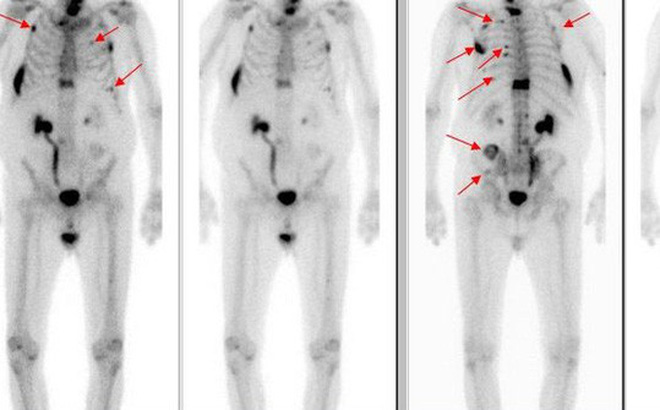

Nếu bạn xuất hiện những triệu chứng trên, bác sĩ sẽ thăm khám kỹ lưỡng, làm xét nghiệm máu và xạ hình xương. Tùy thuộc vào kết quả xét nghiệm cũng nhưng mức độ và vị trí đau xương, bác sĩ sẽ chỉ định cho bạn chụp X-quang, cắt lớp vi tính hoặc chụp PET. Để chẩn đoán xác định, bác sĩ có thể cần sinh thiết mô xương và quan sát dưới kính hiển vi.